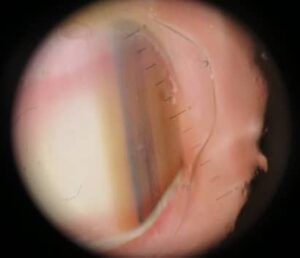

Figuur 3a en b. Melanonychia op basis van een melanoom, met Hutchinson’s sign (2 verschillende patiënten)

Melanonychia kan niet alleen ontstaan door activatie van melanocyten in de nagelmatrix, maar ook door proliferatie van dit celtype. Wanneer die proliferatie maligne is, is er sprake van een subunguaal melanoom. Ook hierbij is het zo dat er veel overeenkomsten zijn tussen een melanoom onder de nagel en op de huid. Plusjé: “Suspect voor een melanoom zijn de naevi die op latere leeftijd ontstaan, een grillige vorm hebben en diverse kleurschakeringen vertonen. Zo ook onder de nagel. We gebruiken de ABCDEF-regel om te bepalen of er sprake kan zijn van een subunguaal melanoom (zie kader).” Plusjé geeft weer voorbeelden aan de hand van foto’s uit zijn eigen praktijk. “De eerste foto toont een melanoom (figuur 3a). De band is breder dan 3 à 4 millimeter, bevat kleurschakeringen, heeft een onregelmatig patroon en geen scherpe afgrenzing. Bij een vergevorderd melanoom ontstaat door aantasting van de nagelmatrix ook onychodystrofie: verstoorde aanleg met splijting van de nagel (figuur 3b).” De kans dat een melanonychia kwaadaardig is, neemt toe met de leeftijd. Dat betekent niet dat melanomen nooit op jonge leeftijd kunnen ontstaan. “Het is uitzonderlijk, maar je kunt het nooit helemaal uitsluiten”, vertelt Plusjé. “Ik heb een patiëntje gehad van een jaar of 12 met een subunguaal melanoom. Je moet dus altijd alert zijn en alle kenmerken in ogenschouw nemen bij de diagnostiek.”

Een alarmsignaal voor de aanwezigheid van een melanoom is daarnaast het Hutchinson’s sign: bruine verkleuring van de huid rondom de nagel, meestal in de nagelplooi, veroorzaakt door pigment van ingroeiende melanoomcellen. “Bij een subunguaal melanoom komt bijna altijd een Hutchinson’s sign voor, al zijn er uitzonderingen”, vertelt Plusjé. Beide foto’s tonen een Hutchinson’s sign (figuur 3a en 3b). Plusjé: “Een zeer sterke aanwijzing voor een melanoom is dus de combinatie van een longitudinale melanonychia in 1 nagel met een Hutchinson’s sign en eventueel ook splijting van de nagel.”